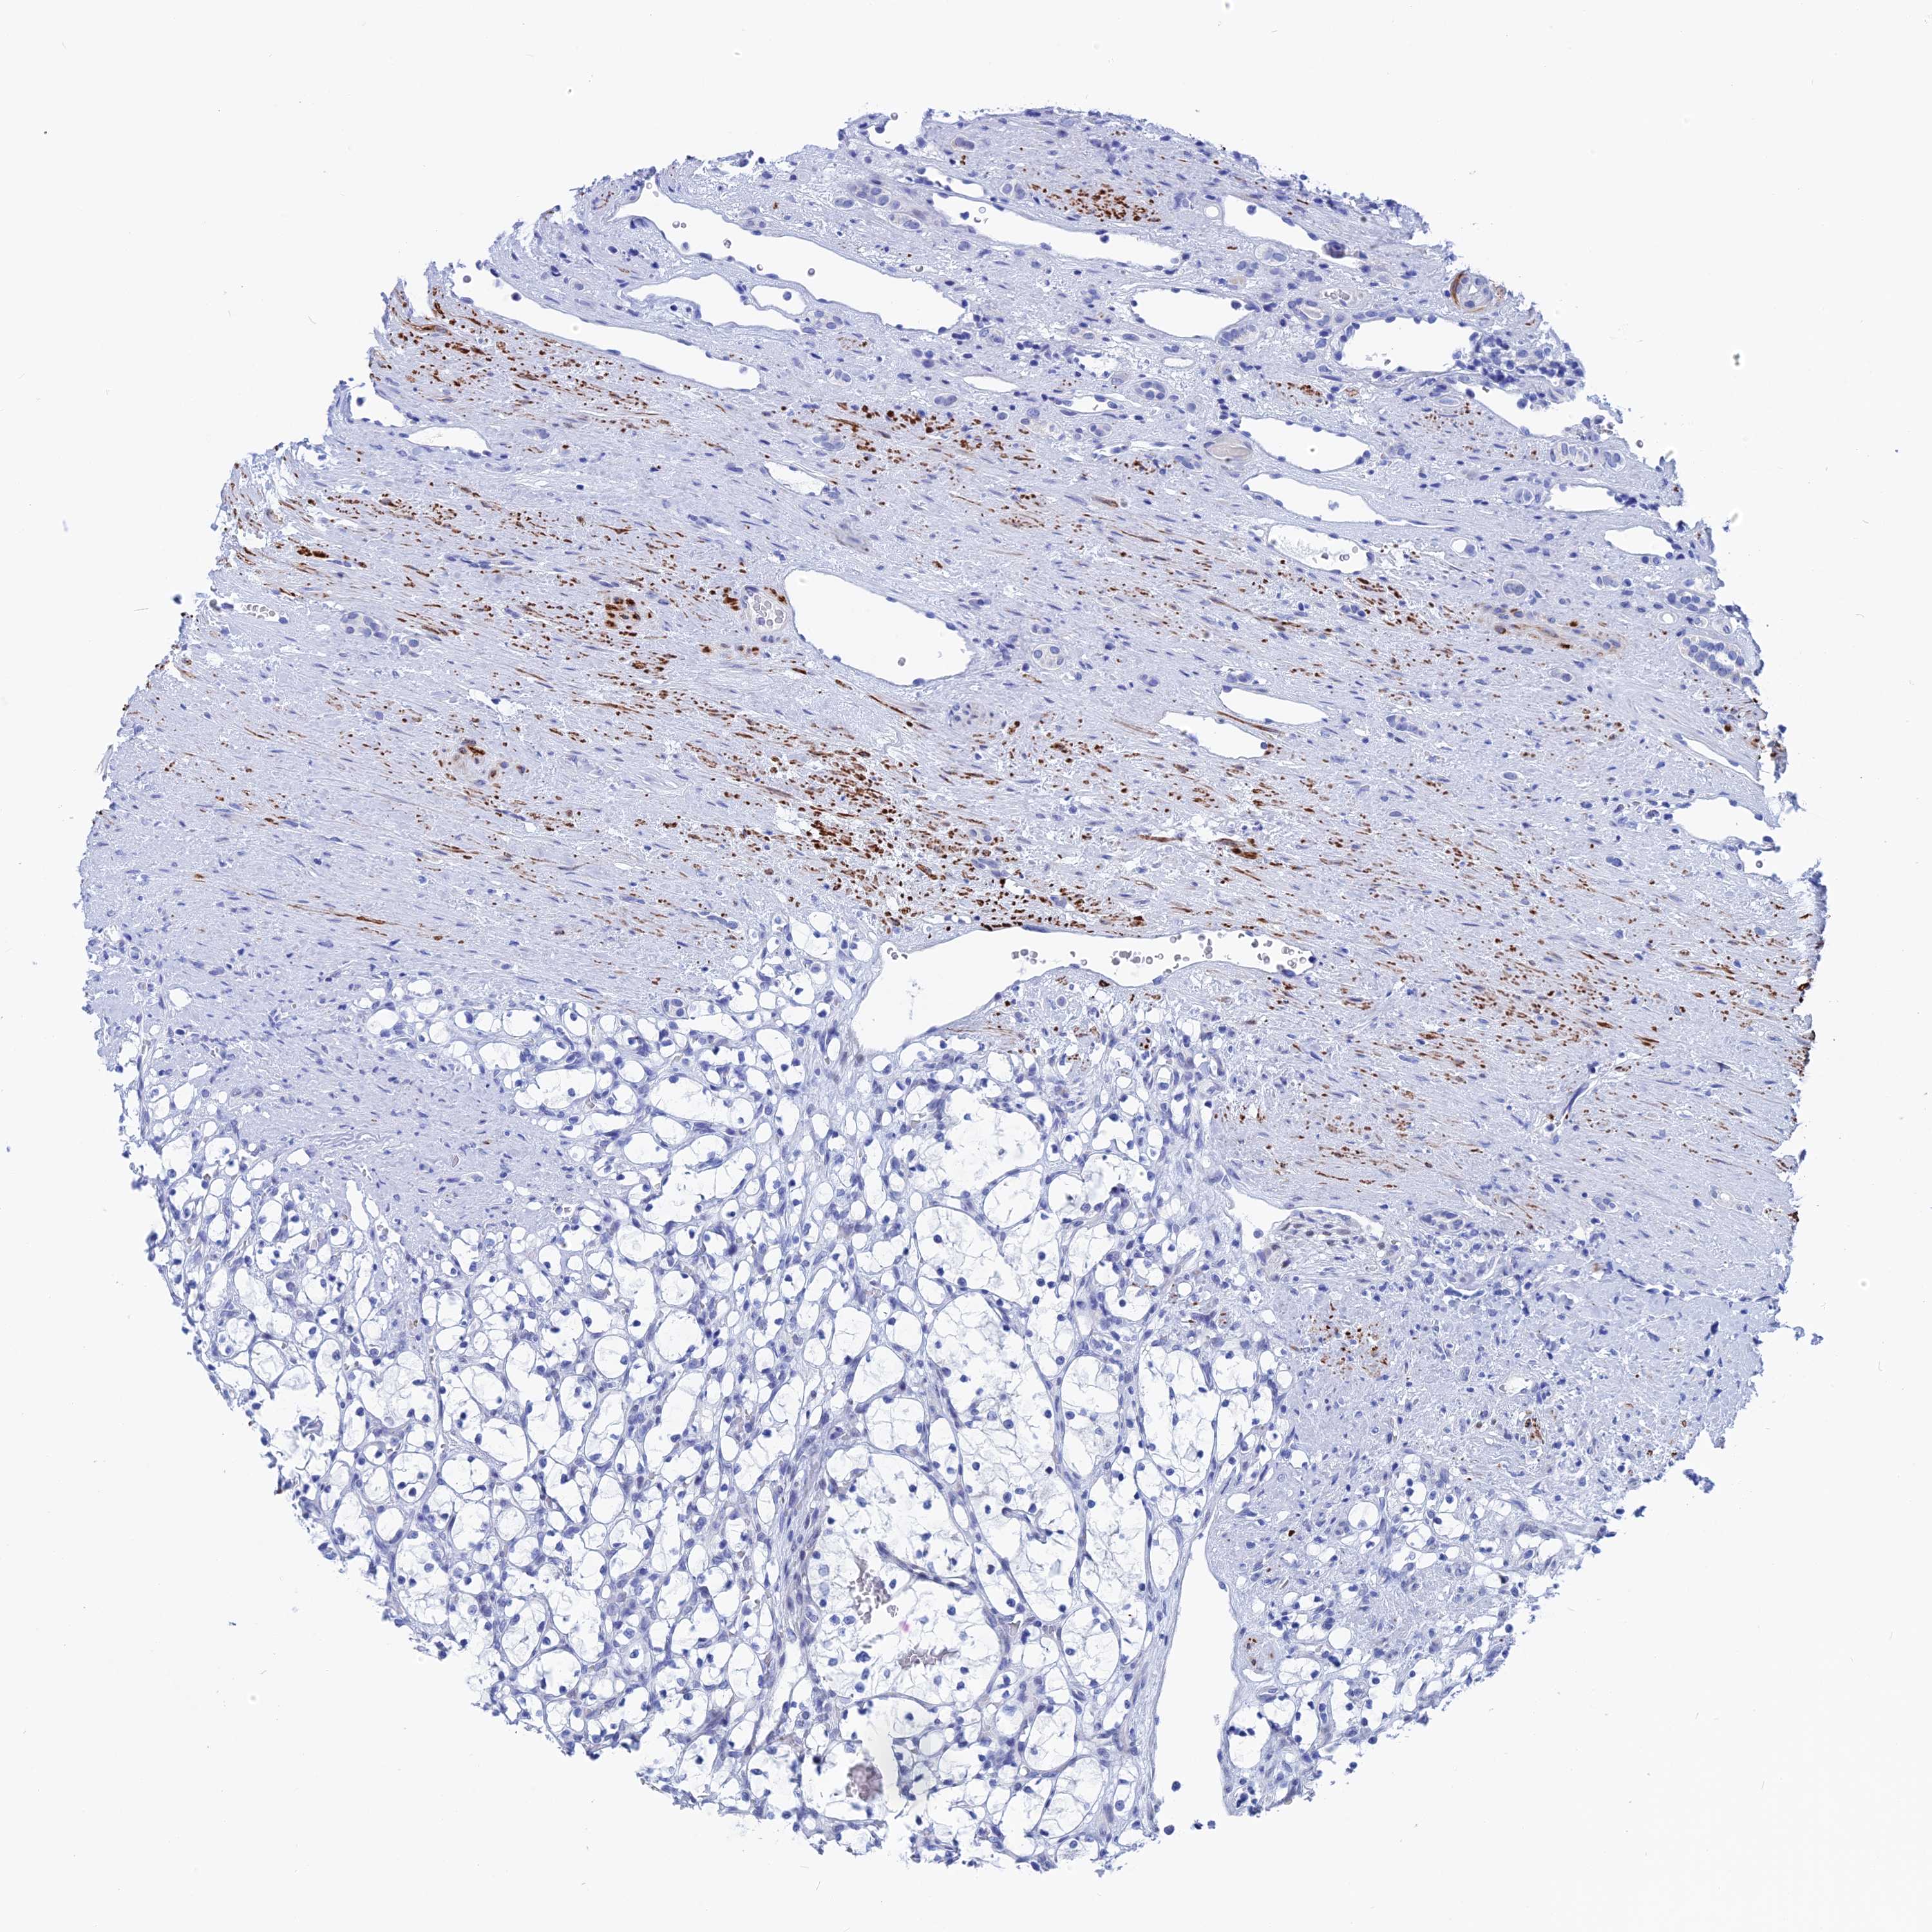

KIDNEY RENAL CLEAR CELL CARCINOMA (VALIDATION) - Interactive survival scatter ploti

The Survival Scatter plot shows the clinical status (i.e. dead or alive) for all individuals in the patient cohort, based on the same data that underlies the corresponding Kaplan-Meier plots. Patients that are alive at last time for follow-up are shown in blue and patients who have died during the study are shown in red.

The x-axis shows the expression levels (FPKM) of the investigated gene in the tumor tissue at the time of diagnosis. The y-axis shows the follow-up time after diagnosis (years). Both axes are complimented with kernel density curves demonstrating the data density over the axes. The top density plot shows the expression levels (FPKM) distribution among dead (red) and alive patients (blue). The right density plot shows the data density of the survived years of dead patients with high and low expression levels respectively, stratified using the cutoff indicated by the vertical dashed line through the Survival Scatter plot. This cutoff is automatically defined based on the FPKM cutoff that minimizes the p-score. The cutoff can be changed by dragging the vertical line or by entering a cutoff value in the square labeled "Current cut-off".

Under the Survival Scatter plot the p-score landscape (black curve; left axis) is shown together with dead median separation (red curve; right axis). Dead median separation is the difference in median mRNA expression between patients who have died with high and low expression, respectively. It is calculated as follows: median FPKM expression of dead patients with high expression - median FPKM expression of dead patients with low expression. This is intended to aid the user in visually exploring custom cutoffs and the associated p-scores and dead median separation.

Individual patient data is displayed and can be filtered by clicking on one or more of the category buttons on the top of the page. Categories describing expression level and patient information include: high, low, alive, dead, female, male and tumor stages. The scale of the x-axis can be toggled between linear and log-scale by clicking on the "x log" button. Mouse-over function shows TCGA ID, patient information and mRNA expression (FPKM) for each patient.

& Survival analysisi

Kaplan-Meier plots summarize results from analysis of correlation between mRNA expression level and patient survival. Patients were divided based on level of expression into one of the two groups "low" (under cut off) or "high" (over cut off). X-axis shows time for survival (years) and y-axis shows the probability of survival, where 1.0 corresponds to 100 percent.

WDR83 is not prognostic in Kidney Renal Clear Cell Carcinoma (validation)

Best expression cut offi

Based on the FPKM value of each gene, patients were classified into two groups and association between prognosis (survival) and gene expression (FPKM) was examined. The best expression cut-off refers the FPKM value that yields maximal difference with regard to survival between the two groups at the lowest log-rank P-value. Best expression cut-off was selected based on survival analysis .

When clicking on this number, the vertical dashed line indicating cut-off, the interactive survival plot, and the Kaplan-Meier curve will be adjusted to show results based on the best expression cut-off.

: 6.14

TCGA RNA samplesi

RNA-seq data is reported as average FPKM (number Fragments Per Kilobase of exon per Million reads), generated by the The Cancer Genome Atlas (TCGA) .

Normal distribution across the dataset is visualized with box plots, shown as median and 25th and 75th percentiles. Points are displayed as outliers if they are above or below 1.5 times the interquartile range. FPKM values of the individual samples are presented next to the box plot.

Average pTPM 7.2

Number of samples 100